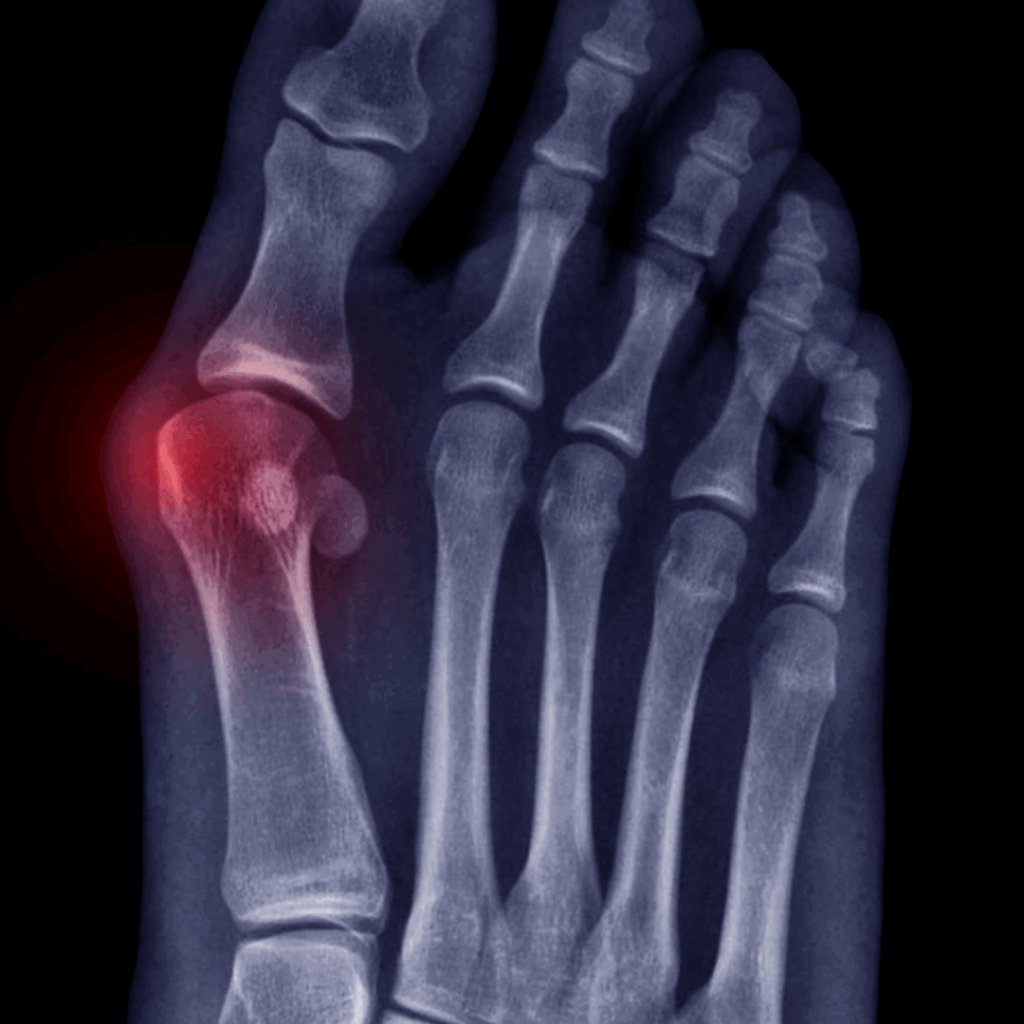

It is believed that once the bunion has become solid, surgery is the only option to remove it and realign the bones in the foot. However, by understanding the fascia system and how to release the pattern of movement that caused it to develop, we can heat the area and awaken the healing proteins to do their job of tissue repair.

We can also change the mechanics of movement that created this in the first place by becoming conscious of our walking and standing posture.